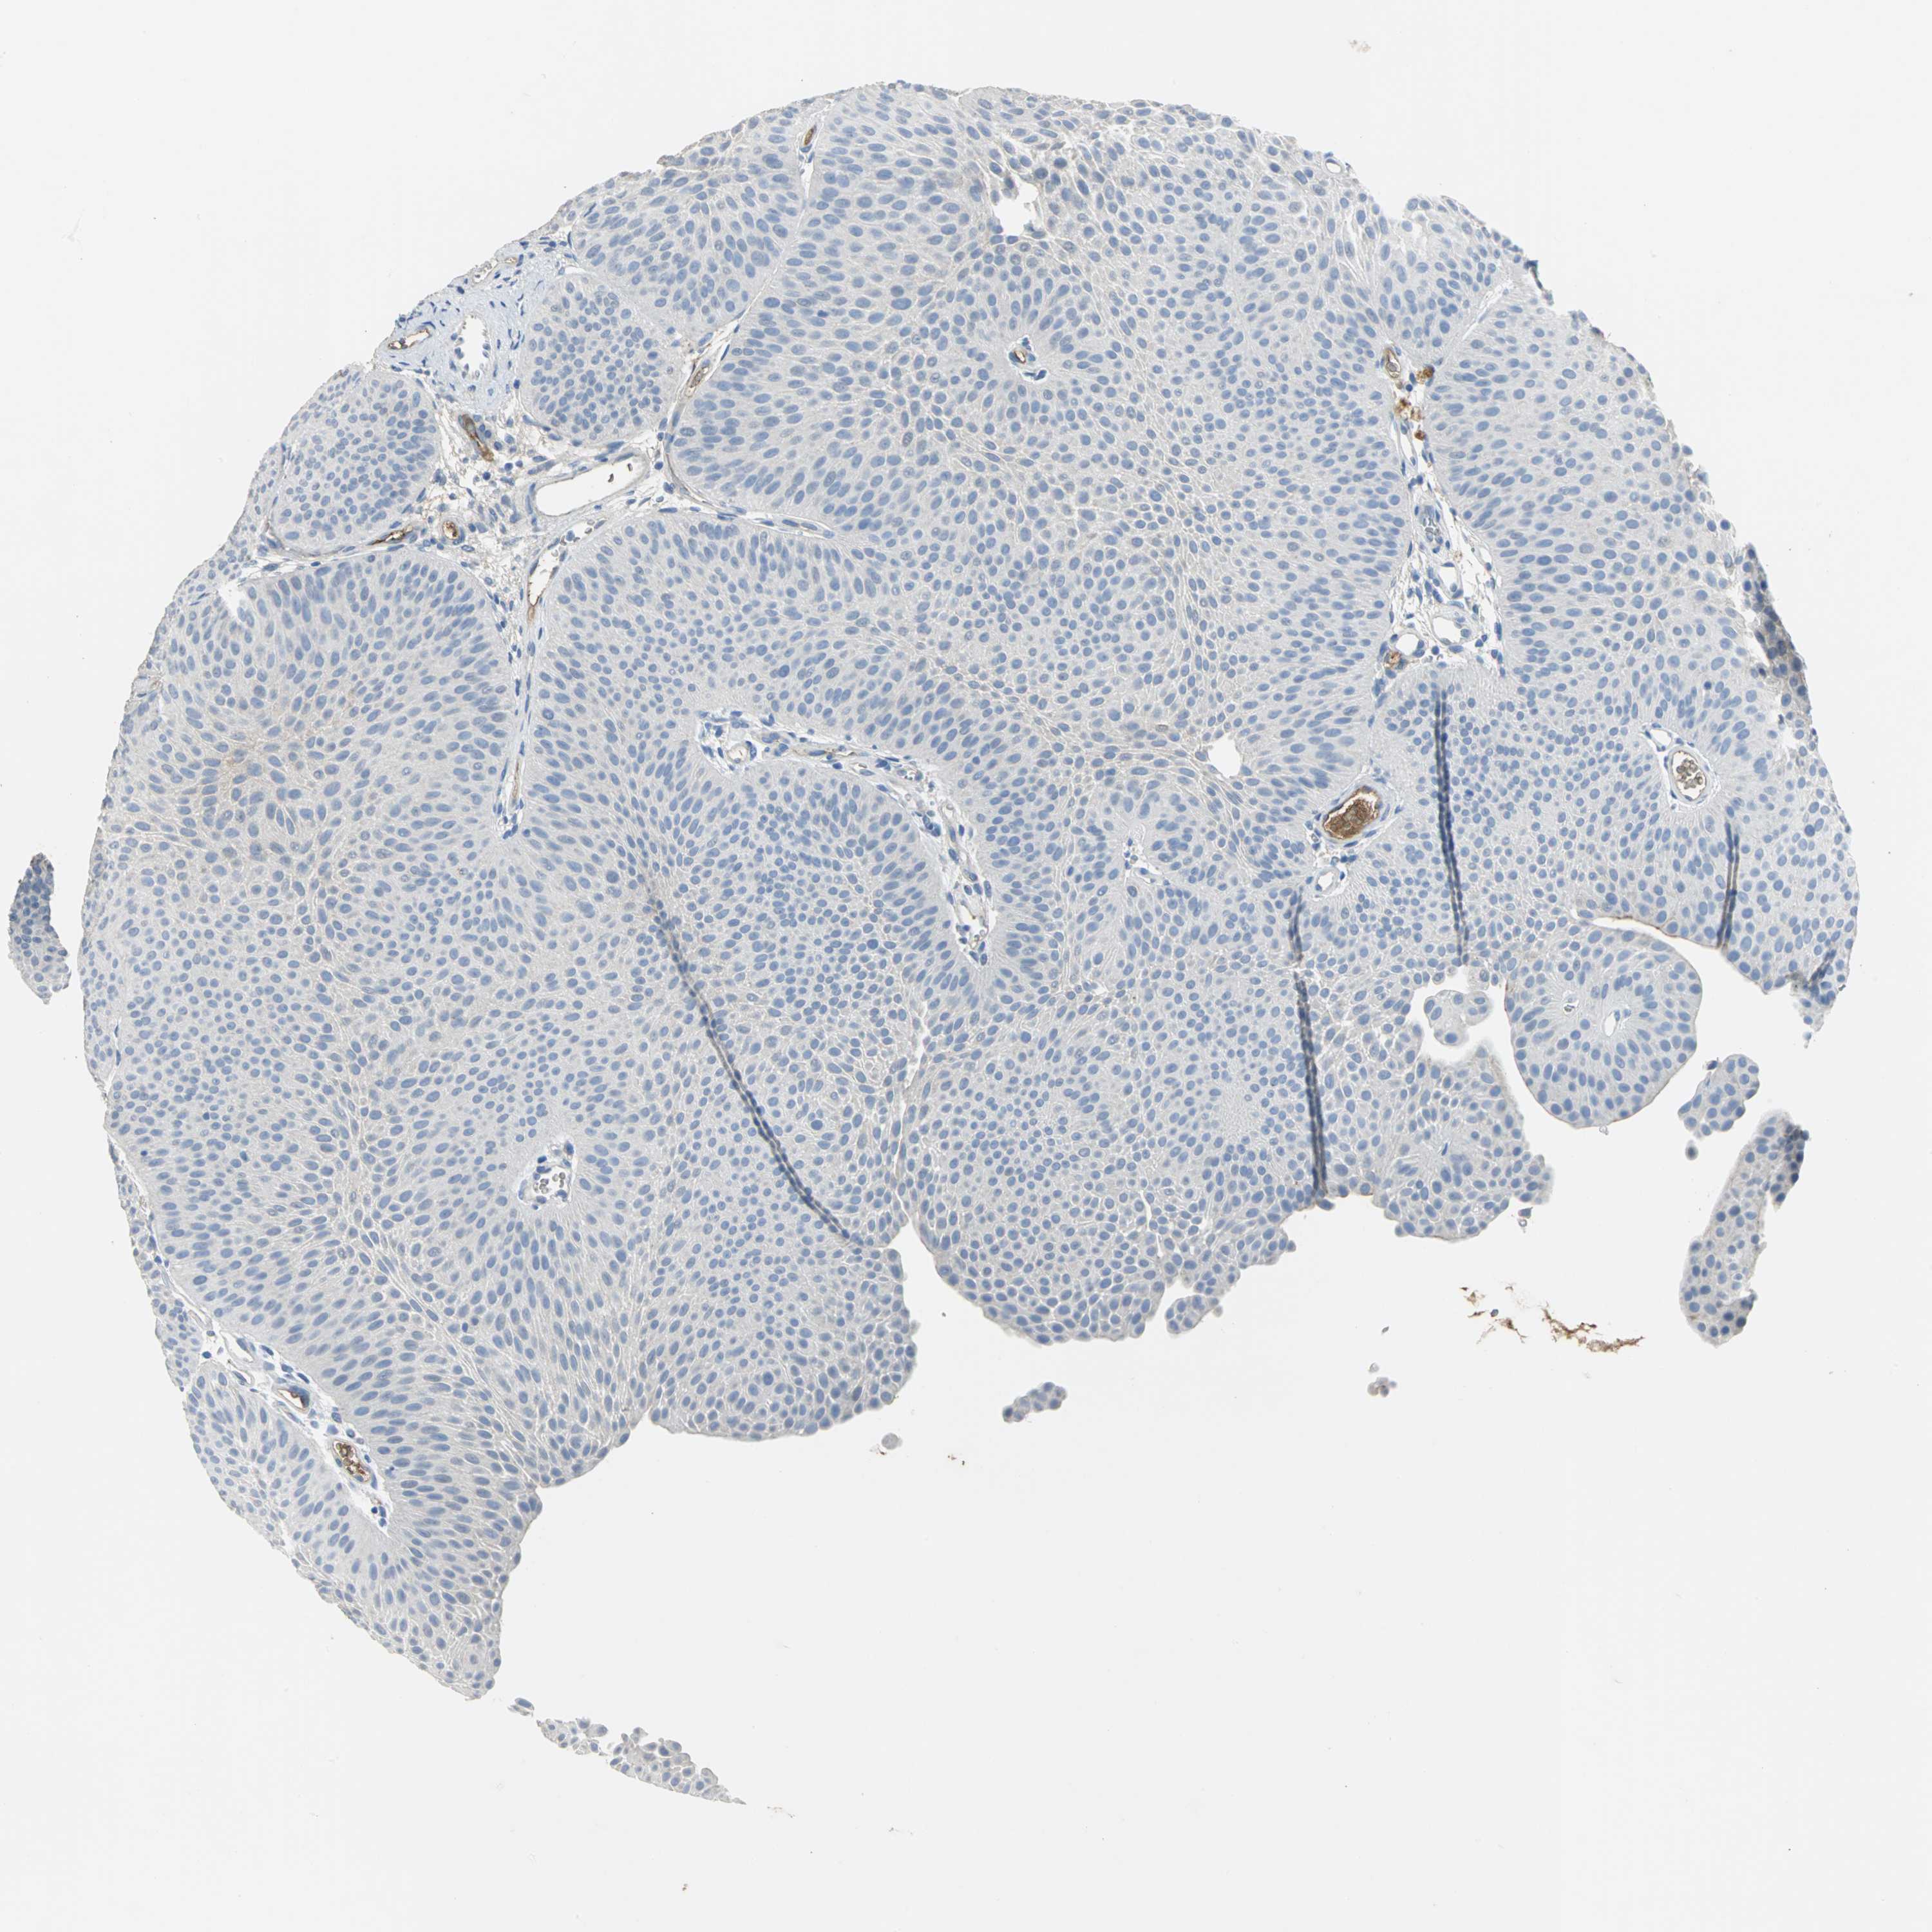

UROTHELIAL CANCER - Protein expressioni

A mouse-over function shows sample information and annotation data. Click on an image to view it in a full screen mode. Samples can be filtered based on level of antibody staining by selecting one or several of the following categories: high, medium, low and not detected. The assay and annotation is described here.

Note that samples used for immunohistochemistry by the Human Protein Atlas do not correspond to samples in the TCGA dataset.

Antibody stainingi

Antibody staining in the annotated cell types in the current human tissue is reported as not detected, low, medium, or high, based on conventional immunohistochemistry profiling in selected tissues. This score is based on the combination of the staining intensity and fraction of stained cells.

Each image is clickable and will lead to virtual microscopy that enables deeper exploration of all samples and also displays staining intensity scores, fraction scores and subcellular localization as well as patient and tissue information for each sample.

Antibody HPA005495

Antibody HPA064686

Staining

High

Medium

Low

Not detected

Intensity

Strong

Moderate

Weak

Negative

Quantity

>75%

75%-25%

<25%

None

Location

Nuclear

Cytoplasmic/membranous

Cytoplasmic/membranous,nuclear

Urothelial carcinoma, High grade

Urothelial carcinoma, Low grade

Urothelial carcinoma, NOS